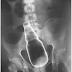

Ini adalah bukti keputusan X-ray dalam yang sangat pelik apabila perkara-perkara tersebut berada dalam organ manusia atau lebih tepat lagi, objek sesuatu barangan yang dimasukkan melalui kemaluan ataupun dubur.